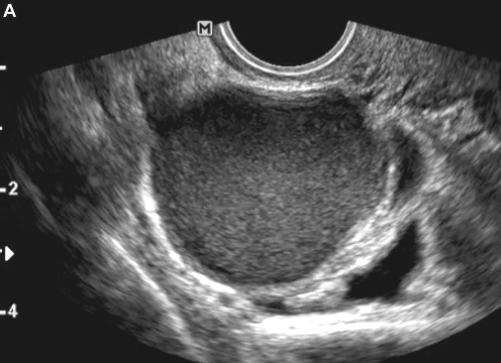

Paciente de 30 anos, G1P1 (C), veio ao consultório com queixas de cólicas de média intensidade no período catamenial há quatro anos, de caráter progressivo, associada à irregularidade menstrual. Sem métodos contraceptivos há dois anos. Traz consigo resultado de ultrassonografia que revela cisto em região ovariana, volumoso, uniloculado, com conteúdo tipo “vidro fosco” e ausência de vascularização ao Doppler.